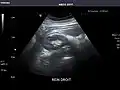

Right kidney